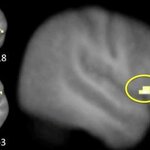

Article teaser image

Excitability Of Motor Neurons Predicts Working Memory

A new paper studied if the excitability of the motor cortex correlates with working memory performance – and results were positive.  By measuring the motor excitability, conclusions can be drawn as to general cortical excitability – as well as to cognitive performance, say the scholars from the Transfacultary Research Platform at the University of Basel. Working memory allows the temporary storage of information such as memorizing a phone number for a short period of time. Studies in animals have shown that working memory processes among others depend on the excitability of neurons…